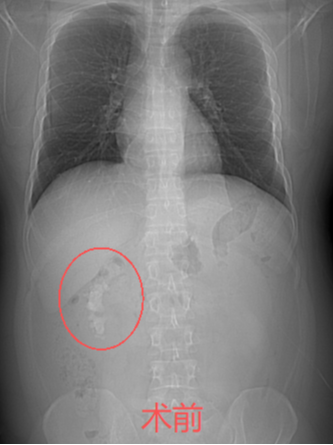

“医生,您帮我看看,我这样的情况能不能不在肾上‘打孔’?”34岁的姚先生拿着自己的CT报告,一脸焦虑地走进市中医医院泌尿外科。报告显示,他的右肾里藏着一颗铸型结石,形状不规则,几乎填满了肾脏空间。外院医生曾建议他做“经皮肾镜碎石取石术”——一种需要在腰部穿刺造瘘的微创手术。一想到术后身上要带着一根肾造瘘管好几天,姚先生犹豫了。泌尿外科副主任杨泽敏仔细阅片后,提出了一个更让他安心的方案——利用先进的高清软镜系统进行“无创清石”,从自然通道进入,碎石的同时直接吸出,体表不会留任何伤口。

效果展示

手术非常顺利,姚先生体内的结石被彻底清除。术后,科室还为他安排了结石成分分析,并开具了个体化的中药汤剂,旨在调理体质,预防复发。从“瞬间清石”到“长期防石”,实现了对泌尿系结石的全程化管理。